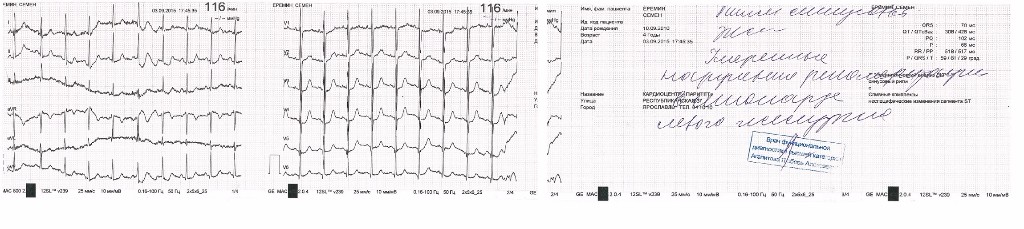

Анализы и обследования: общий анализ крови, мочи, кровь на сахар, экспресс-тест на содержание наркотиков, ЭКГ, ЭХО КГ (по рекомендациям расшифровки ЭКГ), ЭЭГ.